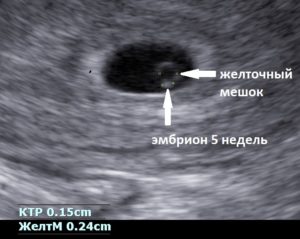

Желточный мешок становится виден во время ультразвукового исследования только к 6 неделе беременности. До этого он слишком мал в размерах, чтобы его можно было рассмотреть. По величине образования, его увеличению или уменьшению врач может судить, нормально ли протекает эмбриональное развитие в утробе матери.

Желточный мешок в норме визуализируется с 6 до 12 недели беременности и представляет собой округлое тонкостенное анэхогенное образование в непосредственной близости от эмбриона. Его диаметр составляет 4-8 мм (на 7-ой неделе от 4-5 мм), постепенно увеличивается до 10 мм, и затем начинается его обратное развитие.

При ультразвуковом исследовании на ранних сроках беременности именно желточный мешок является важным диагностическим критерием. Это обусловлено тем, что размеры желточного мешка в первые девять недель беременности значительно превышают размеры ребенка.

Желточной мешок при беременности начинает визуализироваться с 5,5 недели. При нормально развивающейся беременности на сроке 5-10 недель размер желточного мешка должн быть меньше 5,5 миллиметров.